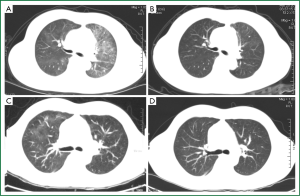

A 46-year-old female was diagnosed with large-B-cell lymphoma, grade IIb, in December 2011 by pathological observations from left supraclavicular lymph node biopsy specimen. On Dec 15th, she was given chemotherapy with Rituximab-CHOP regimen, including cyclophosphamide 750 mg/m2, day 1; doxorubicin 50 mg/m2, day 1; vincristine 2 mg, day 1; prednisolone 100 mg/day for 5 days. Rituximab was given at a dose of 600 mg, day 1. The patient well tolerated the treatment and discharged on Dec 20th with a normal blood white cell count (WBC 8.95×109/L), normal hepatic and renal functions. The chemotherapy was given in three cycles biweekly. Ten days after discharging, the patient presented with bone marrow suppression as peripheral blood WBC lowered to 1.59×109/L. GSM-GF injection was given for continually three days and the WBC counts rose to 21.9×109/L at day 3. On Jan 22nd, the patient presented with chest-tightness and dyspnea but no cough and fever. Chest CT scanning was performed and revealed obvious diffuse ground glass opacities (GGO) with interstitial thickening in both upper lungs (Figure 1A). A diagnostic bronchial-alveolar lavage (BAL) was immediately performed and bronchial-alveolar lavage fluid was collected. Under microscope foamy masses that highly suggestive of pneumocystis jiroveci were observed and the diagnosis was finally established by Giamsa-staining. The patient was given oral TMP-SMZ (400/80 mg, at every eight hours) and corticosteroid (30 mg, daily) therapy. A chest CT scanning three weeks after the TMP-SMX therapy demonstrated a complete disappearance of pulmonary infiltrates (Figure 1B).

A 46-years old male was admitted to our hospital for a mass on left jaw. After operation, pathological examination revealed a diffuse large-B cell lymphoma in salivary gland. Immuno-labeling showed that CD20, CD79alpha, CD21, Ki-67, and bcl-2, 6 were all positive. The patient was wholly accessed and diagnosed as diffuse large-B-cell lymphoma, stage II A, IPI score 0, and given R-CHOP regimen (Rituximab 0.6, day 1, CTX 1.2, day 1, doxorubicin 100 mg, VCR 2 mg day 1, prednisone 100 mg, day 1-5). The patient well tolerated the chemotherapy and discharged on Dec 31st, 2011. The chemotherapy was repeated biweekly for 5 cycles. In March, 2012, he presented with cough, slight chest-tightness, and a fever of 37.5 degrees centigrade. He was admitted to hospital on April 2nd, 2012. Physical examination did not find any abnormal signs of the lung like rale. Peripheral blood cell count was normal (WBC 8.1×109/L, Neutrophilecyte 64%). A chest CT scanning was performed and showed ground glass opacities and enhanced pulmonary infiltrates in right upper lobe of the lung which suggested lung infection (Figure 1C). He was given levofloxacin and cefoperaxone. However the symptoms were not satisfactorily relieved. For the relatively typical manifestations on CT scanning film, special pathogens were suspected and a diagnostic bronchial alveolar lavage was maneuvered. Smear of BAL fluid revealed foamy masses highly suggestive of Pneumocystis jiroveci and Giamsa-staining was further performed. PCP was confirmed by typical morphological features of Pneumocystis jiroveci under microscope and the diagnosis was finally established. Due to a history of allergic to sulfa drugs, he was given Caspofungin (50 mg daily with 70 mg at day 1) instead of TMP-SMZ beginning on April 7th. The symptoms were relieved remarkably within a week. A Chest CT scanning was performed on April 12th, and demonstrated that most of the patches were absorbed and the pulmonary infiltrations were reduced (Figure 1D). For the satisfactory result of anti-Pneumocystis jiroveci treatment and no contradiction of chemotherapy, the patient accepted further R-CHOP chemotherapies. The patient was given 7 cycles of R-CHOP regimen all together. PCP was not found during the later chemotherapies.